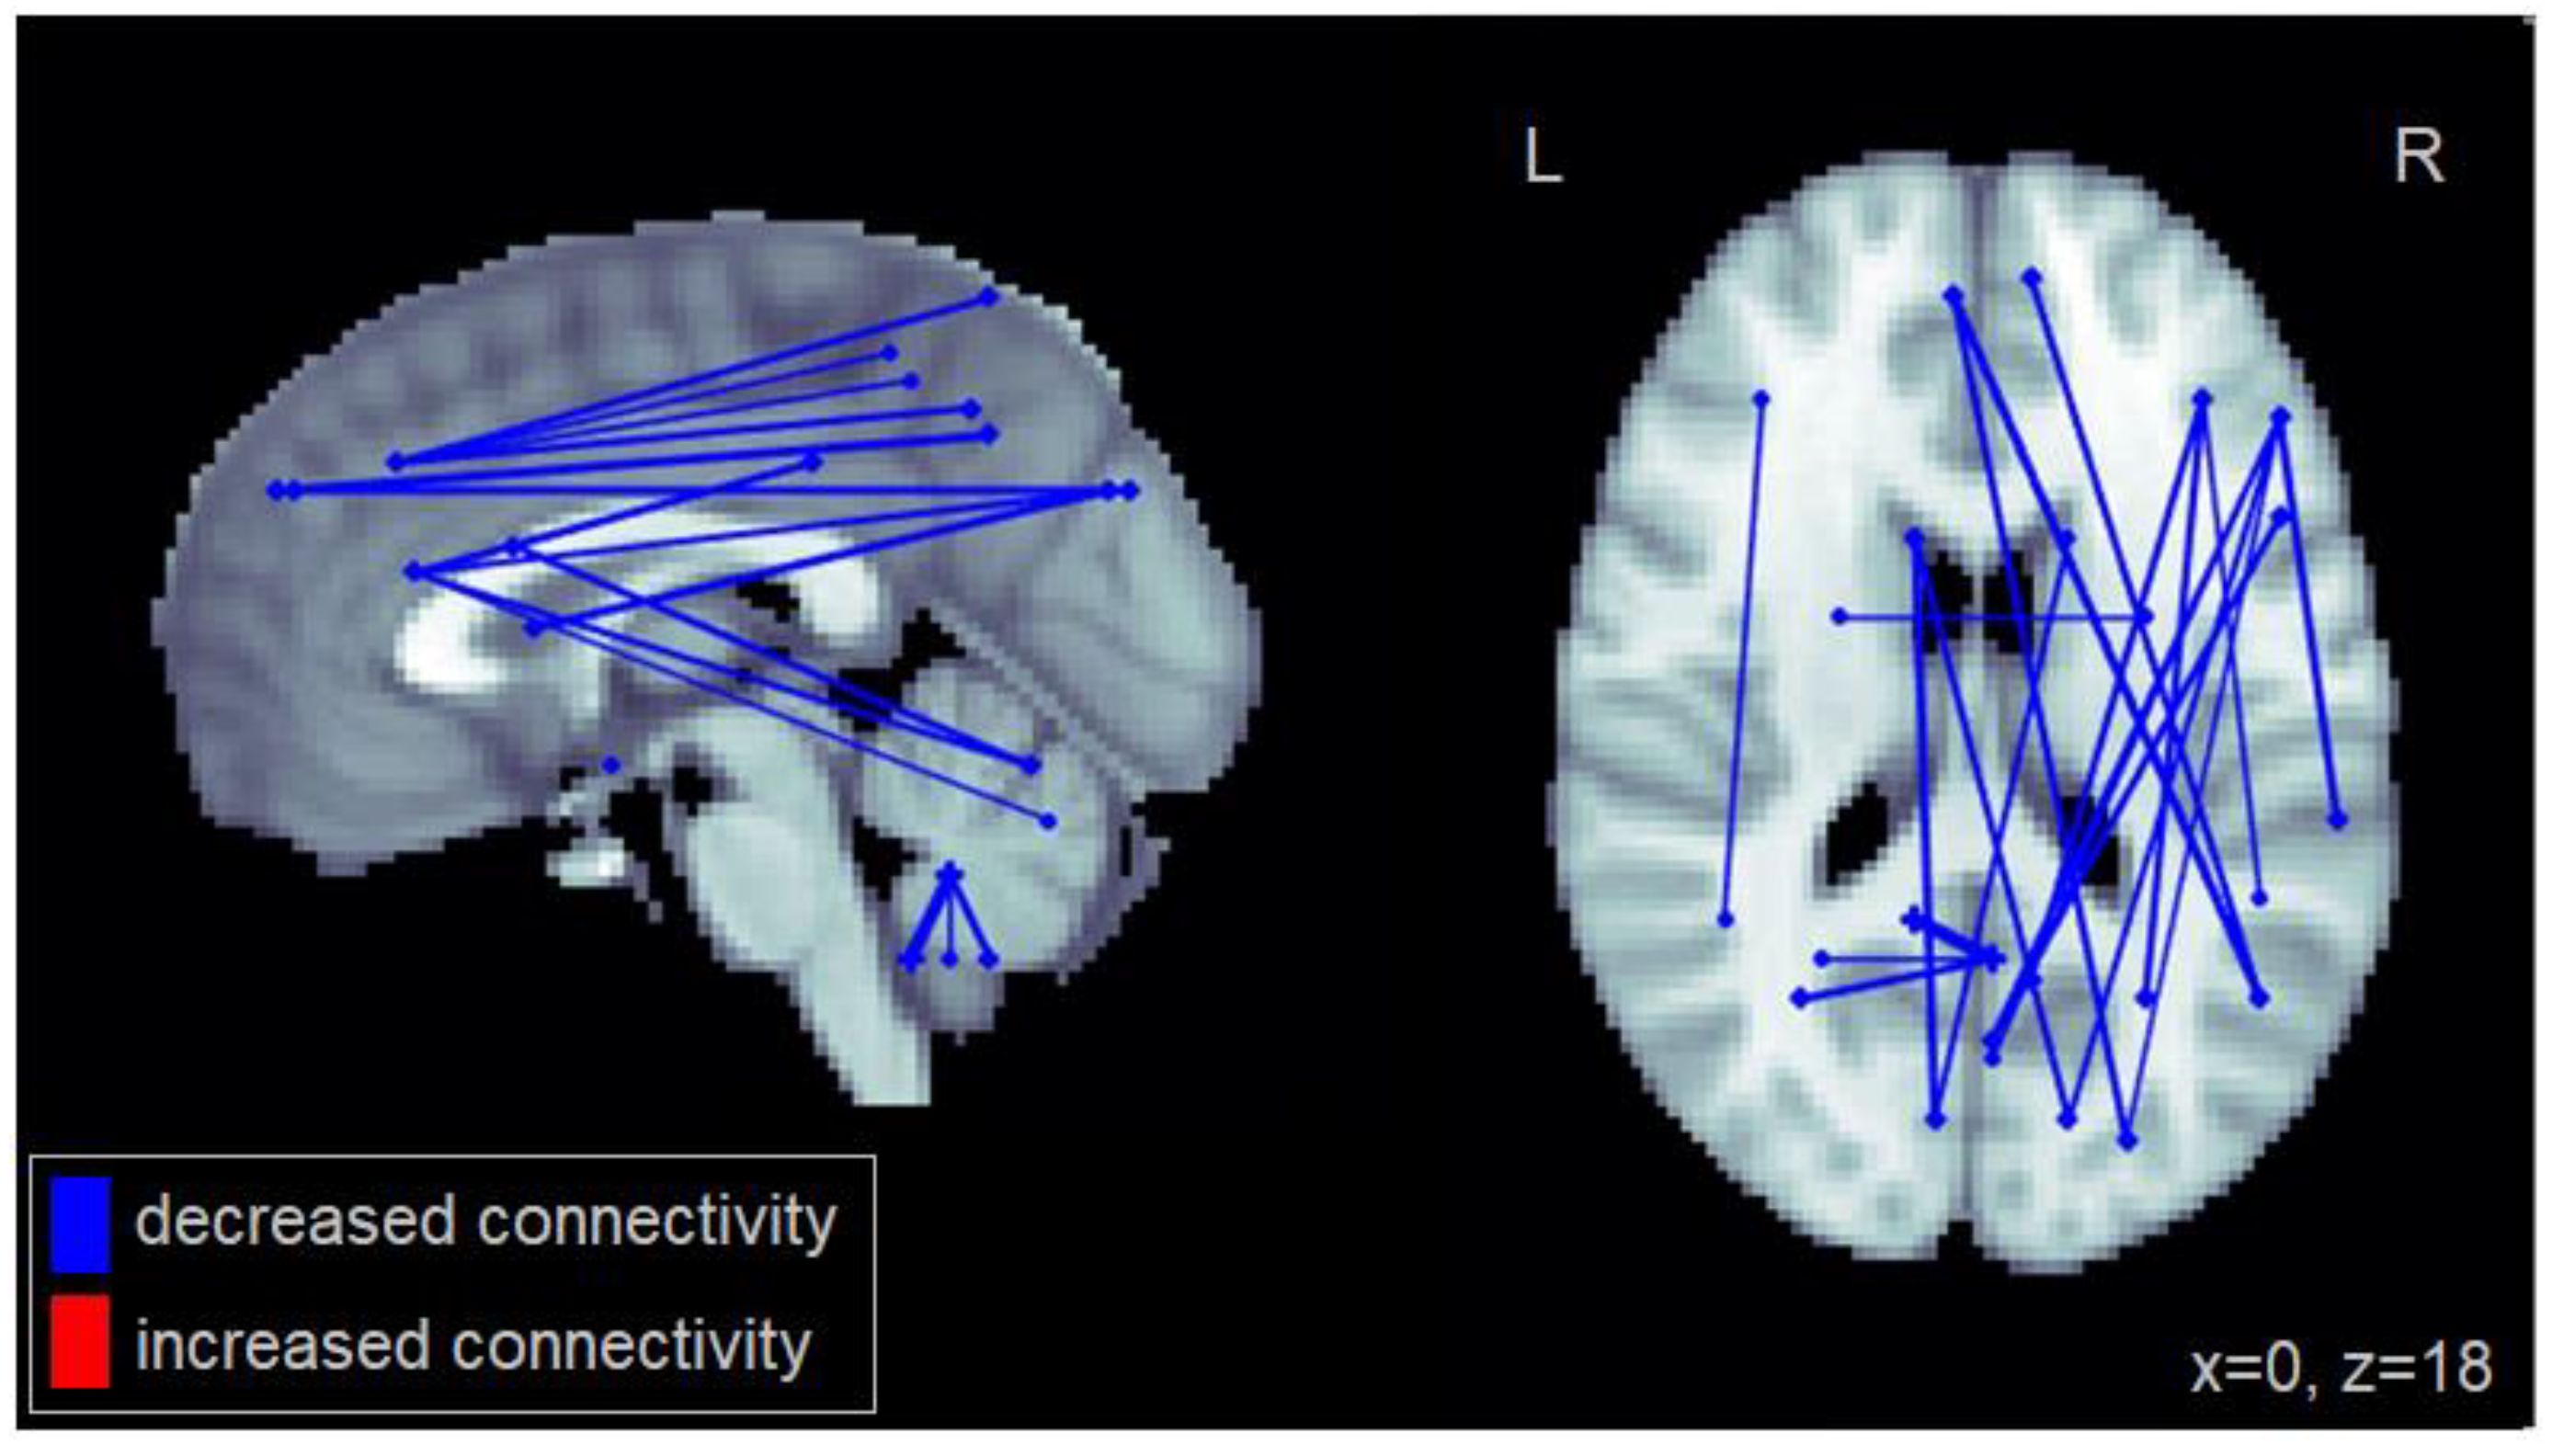

Compared to healthy controls, patients with MCI generally showed reduced functional connectivity, particularly long-distance connections between frontal and posterior cortical regions (Figure 1). Specifically, the MCI group exhibited reduced connectivity between the middle frontal cortex and the superior and inferior parietal cortex; between the superior medial frontal cortex and the superior occipital cortex and the angular gyrus; and between the inferior frontal gyrus and the cuneus as well as the superior occipital cortex. Reduced connectivity was also observed between the inferior orbitofrontal cortex and the cerebellum, within the cerebellum, and between the caudate and the cuneus. The complete set of regions showing reduced connectivity among patients with MCI is reported in Table A1.

Figure 1.

Altered functional connectivity observed for the MCI group compared to the healthy control group. Blue lines denote functional connections with reduced connectivity in MCI patients, red lines denote increased connectivity (significant at FDR = 0.05). Connections are shown as projections in the sagittal and axial plane, with MNI anatomical underlays (slices at x = 0 and z = 18 respectively).